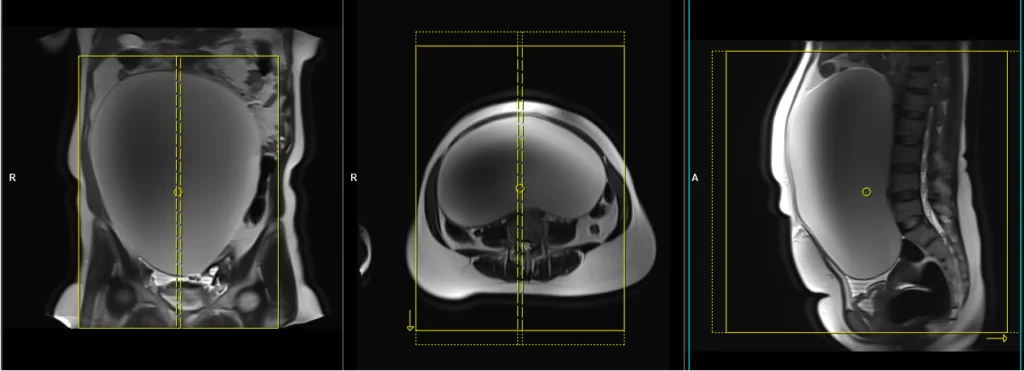

T2 tse axial large FOV 5mm multiple breath hold / respiratory gated

Plan the large field of view (FOV) T2 axial slices on the coronal plane, positioning the block parallel to the line along the right and left iliac crest. Verify the positioning block in the other two planes as well. Establish an appropriate angle in the sagittal plane, perpendicular to the lumbar spine. Ensure that the slices cover the entire pelvic and abdominal mass from top to bottom. The field of view (FOV) should be sufficiently large to encompass the mass, typically ranging from 350mm to 400mm. Use right-to-left phase direction with an adequate level of phase oversampling to prevent any wrap-around artifacts.

Due to the large number of slices, the scan is split into four breath-hold acquisitions, each around 20 seconds long. Instruct the patient to hold their breath during the image acquisition. If T2 TSE scans are not available on your scanner, please use TSE-based single-shot sequences (e.g., HASTE). If the patient is unable to hold their breath, consider using respiratory-gated sequences or radial k-space sequences (e.g., BLADE T2). Using saturation bands above and below the planning block can minimize breathing, pulsation, and peristalsis-related artifacts.

Parameters